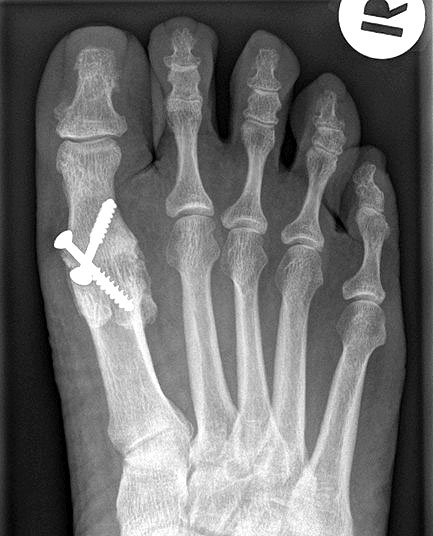

• Röntgenaufnahmen des Vorfußes (unter Belastung) im dorsoplantaren und seitlichen Strahlengang (Abb. 1a+b)

Gekreuzt eingebrachte Schrauben werden immer noch als kostengünstige Standardtechnik der Osteosynthese beschrieben und können bei kräftigen und stabilen Knochenverhältnissen und entsprechender Erfahrung prinzipiell verwendet werden 141516. Der Einsatz kanülierter Schrauben unter Durchleuchtung erleichtert die Operation.

Pseudarthrose: Verzögerte Knochenheilung und Pseudarthrosen treten je nach Osteosynthesetechnik unterschiedlich häufig auf. Bei Verwendung von Drähten oder Drahtcerclagen werden hohe Pseudarthroseraten von über 13% beschrieben, daher sollten diese Verfahren verlassen werden1021. Einzelschrauben bieten keine ausreichende Rotationsstabilität und werden daher nur noch selten verwendet. Korrekt eingebrachte gekreuzte Schrauben ergeben zwar bei primärem Hallux rigidus und guter Knochenqulität eine hohe Stabilität, sind jedoch bei osteopenischem Knochen und vor allem bei rheumatoider Arthritis oft unzureichend 141516. Die Rate an Pseudarthrosen kann hier durch Plattenosteosynthese mit interfragmentärer Zugschraube oder mit winkelstabiler Platte mit Gleit-/Kompressionsloch deutlich gesenkt werden 622. Nachteilig ist die Materialstärke der winkelstabilen Platte die zum Teil vermehrt aufträgt und daher gelegentlich die Metallentfernung notwendig macht.